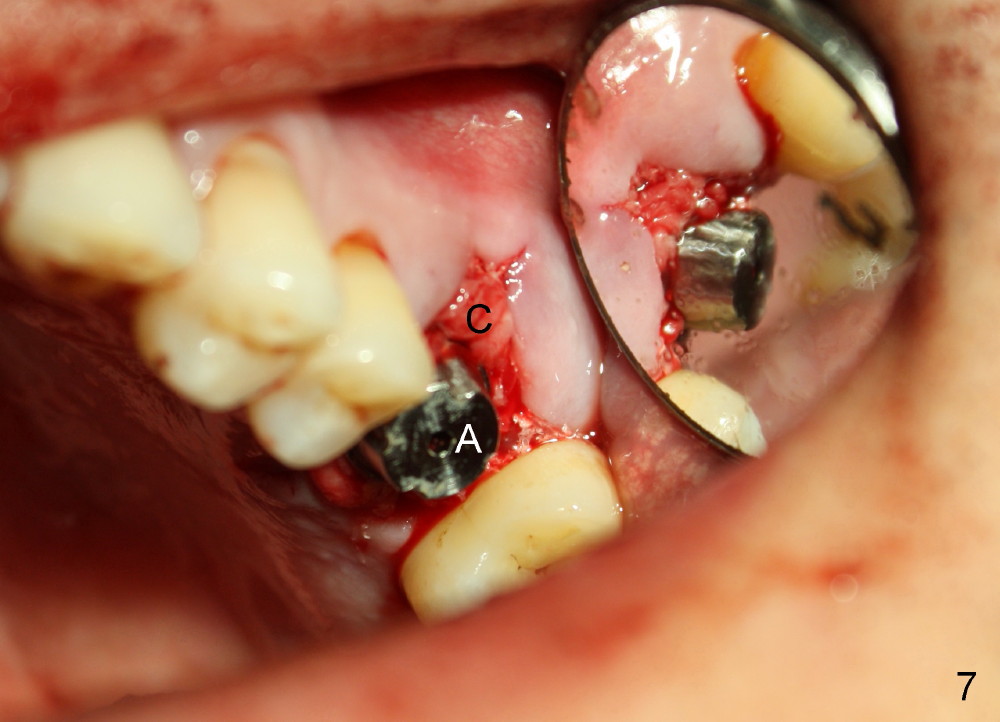

Bone density around the molars (including apical to #14) (Fig.1 black *) is higher than that around the premolar (white *). In fact the tooth has horizontal root fracture (Fig.2: <: CEJ), consistent with high bone density (strong mastication). An immediate implant is planned (Fig.3). After extraction, osteotomy starts at the buccal slope of the palatal (Fig.4 P) socket. Because of high bone density apical to the sockets, drills are required for osteotomy in the septum (type II bone) instead of osteotomes and primary stability is easily achievable (>60 Ncm). When a 7 mm implant (Fig.6 I)) is placed, the peri-implant gaps are much smaller (*) than that with a 4.5 mm tap (Fig.5 T). This helps bone grow faster toward implant. A long implant (17 mm) is necessary for this case to obtain primary stability in the apical one (double arrows in Fig.6). With reamers, a fair amount of autogenous bone is harvested during drilling, mixed with allograft and synthetic bone and placed in the remaining buccal (Fig.7) and palatal (Fig.8) sockets. The openings of the buccal and palatal sockets are covered with collagen dressing (C) and perio dressing. The latter is kept in place by a short abutment (Fig.6-8 A).